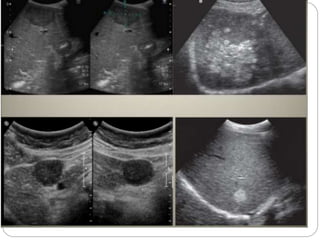

USG  USG -vary  Small HCC’s (<3cms) -> hypoechoic with posterior acoustic enhancement ( fatty change/ marked sinusoidal dilatation)  >3cms- mosaic or mixed pattern  May invade poratl vein  CD:central vascularity

 USG - vary

 Small HCC’s (<3cms) ->

hypoechoic with posterior

acoustic enhancement ( fatty

change/ marked sinusoidal

dilatation)

 >3cms- mosaic or mixed pattern

 May invade poratl vein

 CD:central vascularity